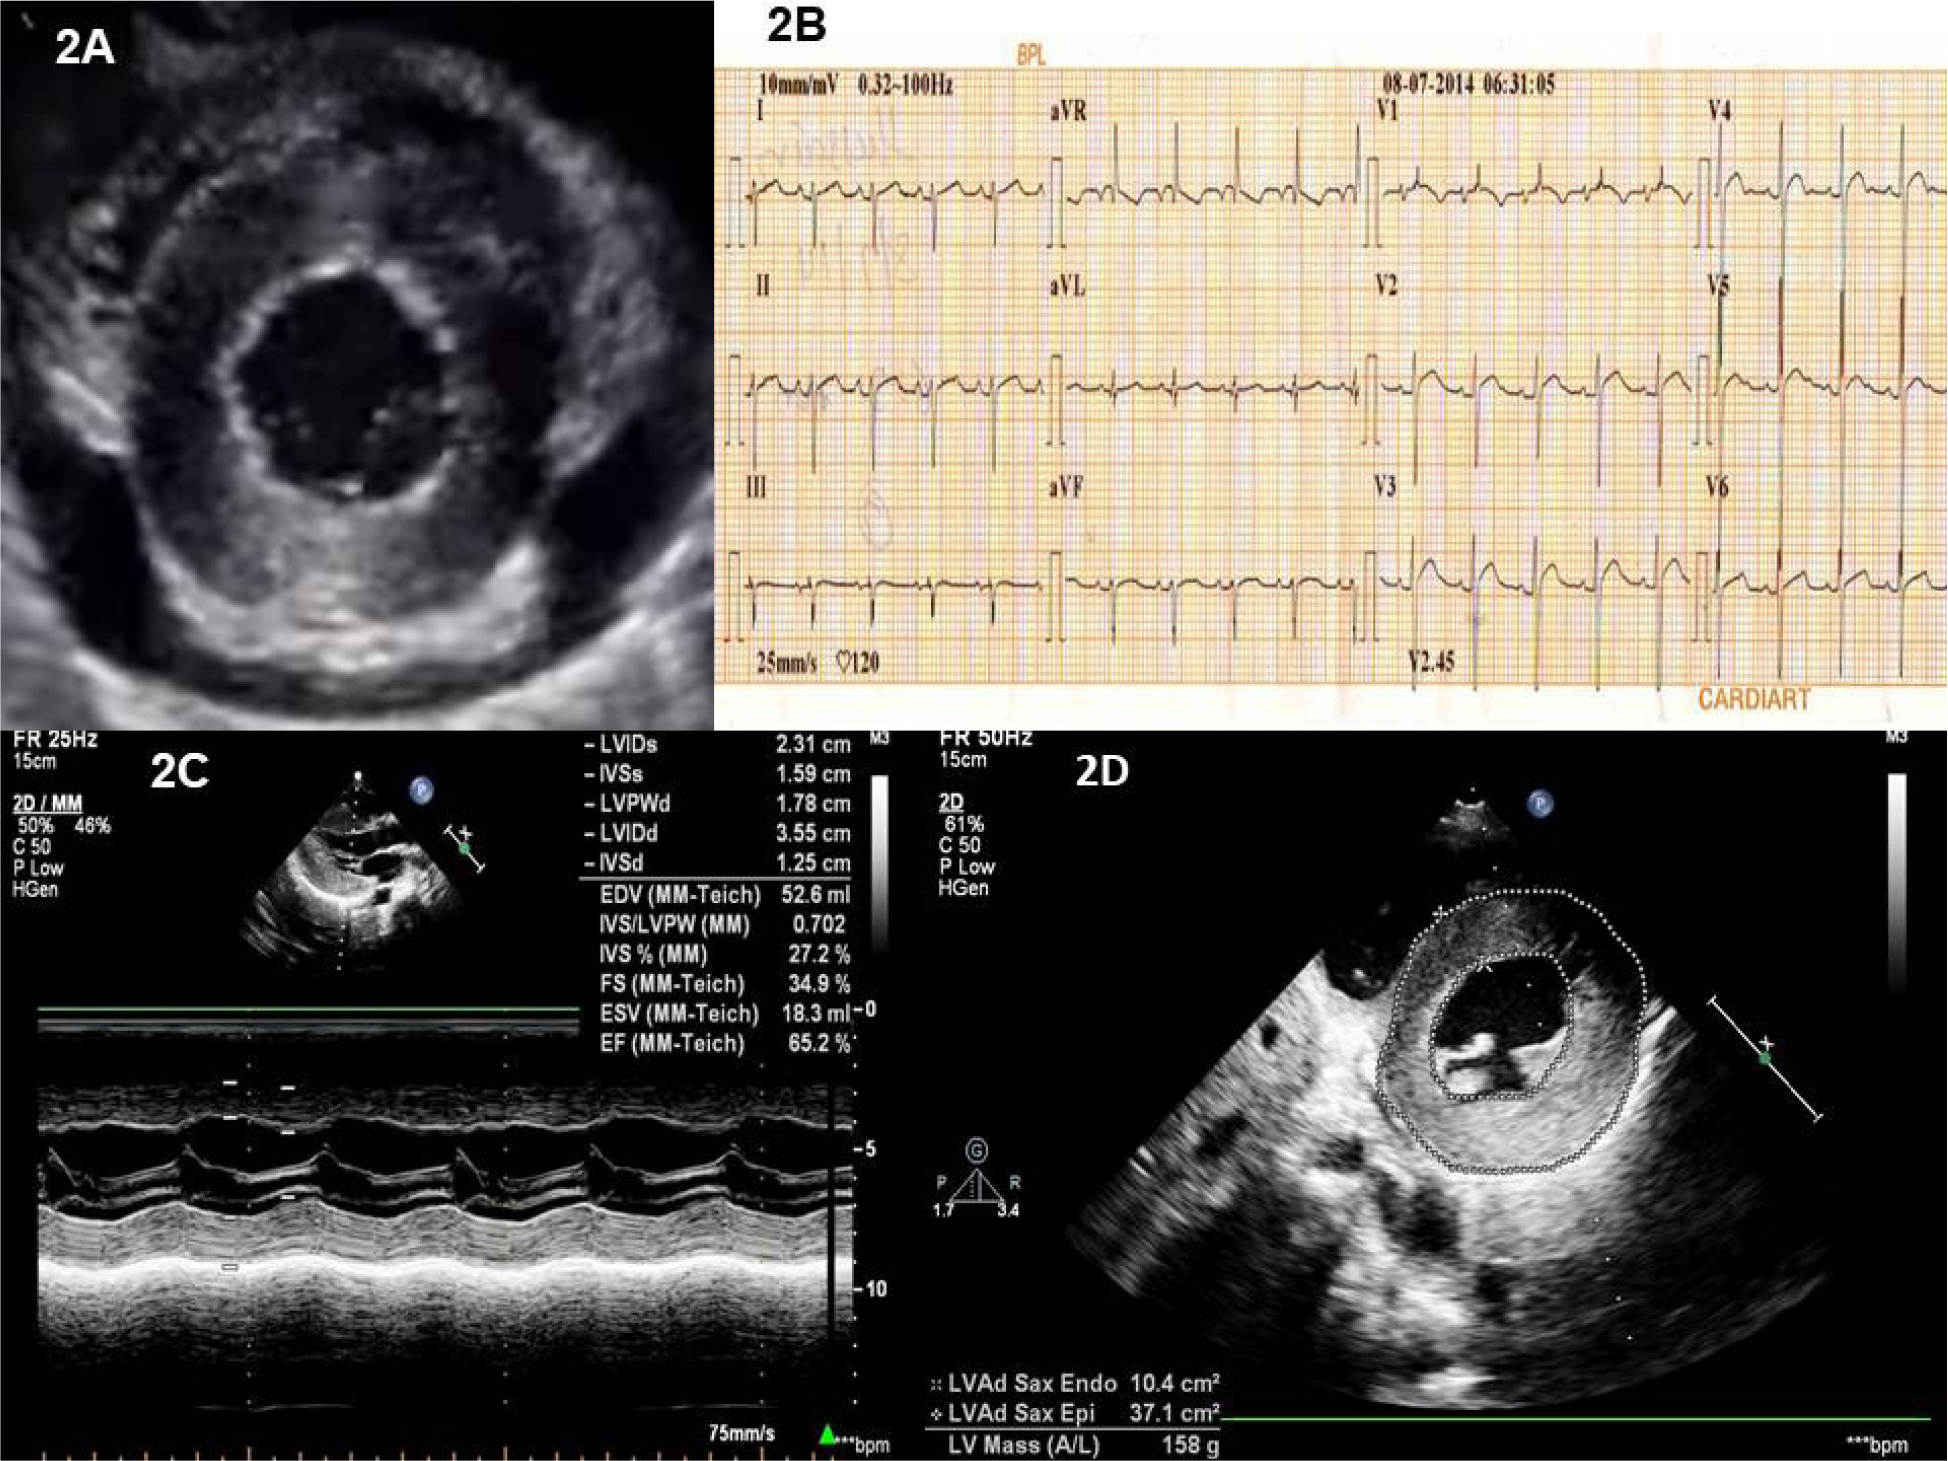

The echocardiography showed moderate pericardial effusion with a maximum diameter of 1.6 cm (Figure 2A). There was subtle right atrial and right ventricle collapse in early diastole in favor of cardiac tamponade. The asymmetrical thickness of the walls of the left ventricle was noticed.

His biochemical profile showed hemoglobin of 12.6 gm per deciliter, the white blood cell count of 6,800cell/mm3 with neutrophils of 65%, lymphocytes of 30%, monocytes of 01%, and eosinophils of 3%. The erythrocyte sedimentation rate was 10 mm 1st hour. Repeat ECG showed no electrical alternans (Figure 2B). The echocardiographic examination revealed normal left ventricular function (Figure 2C). There was increased relative wall thickness, asymmetric hypertrophy of LV, and increased LV mass of 158 gms. The LV mass when indexed to height 2.7 was 99g/m which is severely abnormal increased LV mass for his age [1] (Figure 2D). There was no subsequent fluid accumulation.

Figure 2: A) Echocardiographic image of the parasternal short axis of the left ventricle at the mid-ventricular level showing moderate circumferential pericardial effusion. Concentric left ventricular hypertrophy is also evident. The pericardium is normal. B) Electrocardiogram after pericardiocentesis showing the absence of electrical alternans. There is biventricular hypertrophy by voltage. There is biatrial enlargement and t wave inversion in lead V1. C) The M mode of the left ventricle just below the mitral leaflets showing normal left ventricular function. The relative wall thickness is 1.00. 2D). LV mass calculation by area length method - a value of 158 gm, when indexed to height 2.7 was 99 (indicating severe abnormal increased LV mass) [1].